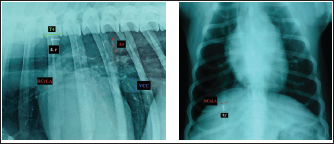

Fig. 1. A and B. Measurements of LA and SA in LL (A) and DV (B) views, with marked T4, S4, M, TI length: LA – long axis, SA – short axis, T4 - the length (mm) of the body and caudal disc of the T4vertebra, S4 - the length (mm) of the S4, M – the length (mm) of the M, TI - the length (mm) of a dog’s TI. Modified vertebral heart sizeThe cardiac LA and SA in LL view were measured as previously described, added up, and then transformed from mm into whole and 0.01 of VHS units (v), by dividing the sum of both axes by the length (mm) of the body and caudal disc of the T4 (VHS-LL) (Spasojević Kosić et al., 2007). The same was done to calculate the cardiac VHS in DV radiographs (VHS-DV). Manubrium heart scoreThe sum of the measured cardiac LA and SA (in mm) was normalized by the corresponding M length (mm) according to the method described by Mostafa and Berry (2017). The same was done for both MHS in LL and in DV radiographs (MHS-LL and MHS-DV). Sternebral heart sizeTo determine SHS, the length of the S4 is used as a unit of measurement. The sum of the measured LA and SA in mm was divided by the length of the S4, both for LL and DV radiographs, in order to get SHS in LL and DV (SHS-LL and SHS-DV). Thoracic inlet heart sizeThe sum of LA and SA (mm) was divided by the length of a dog’s TI. The shortest TI was measured from the craniodorsal M to the cranioventral first thoracic vertebra as described by Marbella Fernández et al. (2023a). For this method, cardiac silhouette measurement was performed only in LL radiographs (TIHS-LL). Cardiac sphericity indexCSI was calculated by dividing the cardiac SA by LA obtained from LL and DV radiographs (CSI-LL and CSI-DV) (Guglielmini et al., 2012). Measurement of blood vesselsObjective methods for assessment of blood vessels relevant to the HWD included several measurements (Fig. 2A and B) and calculations. The diameters of blood vessels relevant for the HWD (RCrLA, RCaLA, and VCC) were first measured and expressed in absolute values (mm). The diameters of the vessels were measured perpendicular to their LA. Relative measurements of the relevant blood vessels were expressed as ratios to the T4 (for all three blood vessels), and to the 4.r (for the RCrLA and VCC), to the 9.r (for the RCaLA), and to the Ao (for the VCC). The T4 was measured as described in modified VHS methods. The measurement of the 4.r was done on its proximal part as the smallest diameter. The measurement of the 9.r was measured at its intersection with the RCaLA. The Ao was measured at the descending part (Herrtage and Denis, 1997; Lehmkuhl et al., 1997; Arya et al., 2021).

Fig. 2. A and B. Measurements of blood vessels relevant to the HWD in LL (A) and DV (B) radiographs: RCrLA – the width (mm) of the RCrLA, VCC – the width (mm) of the VCC, Ao – the width (mm) of the Ao, T4 – the length (mm) of the body and caudal disc of the T4 vertebra, 4.r – the width (mm) of the 4.r, RCaLA – the width (mm) of the right caudal lobar artery, 9.r – the width (mm) of the ninth rib. Ethical approvalAccording to the national law, an ethical approval for this research was not needed. However, a written consent was obtained from the owners. This study was carried out in compliance with the existing animal welfare laws in Europe. Statistical analysesA commercial software package TIBCO Statistica was used for the following statistical analyses: descriptive statistics, the correlation coefficient (r) and coefficient of determination (R2), the Fisher probability test, and the Wilcoxon matched pairs test. The prevalence of subjective radiographic parameters was expressed in absolute and relative numbers (percentages). The correlations between skeletal units (T4, M, S4, TI), as well as between LA, SA, the sum of LA and SA with skeletal units of heart size, were assessed. The correlation was classified as negligible (r=0.00–0.09), weak (r=0.10–0.39), moderate (r=0.40–0.69), strong (r=0.70–0.89), and very strong (r=0.90–1.00). In order to assess the occurrence of subjective parameters of cardiomegaly and abnormal lung patterns in the dogs with HWD before and after therapy the Fisher probability test was used. The Fisher probability test was followed by the post hoc false discovery rate (FDR) test (Benjamini and Hockberg, 1995). The objective parameters of radiographic assessments (cardiac size and shape, and blood vessels measurements) were expressed as the mean ± SD, as well as the minimum and the maximum. The same parameters in the dogs with HWD before and after therapy were assessed by using the Wilcoxon matched pairs test. A probability value of p < 0.05 was considered as significant. ResultsIn 2 out of 40 dogs (2/40 dogs or 5% of dogs), radiographs could only be assessed subjectively. These two dogs had the most severe radiographic features in the areas of lung fields, which made it impossible to assess their cardiac silhouette and vascular pattern, either subjectively or objectively (Fig. 3A–D).